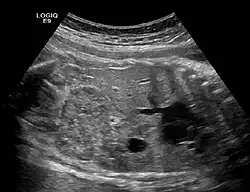

![]() | |

Ectopic crossed fused kidney in a fetus approx. 34 weeks | |